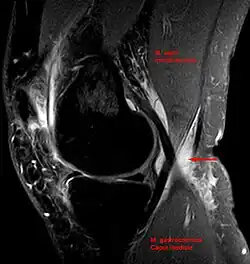

Baker's cyst on axial MRI with communicating channel between the semimembranosus muscle and the medial head of the gastrocnemius muscle. -